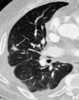

Transbronchial biopsy